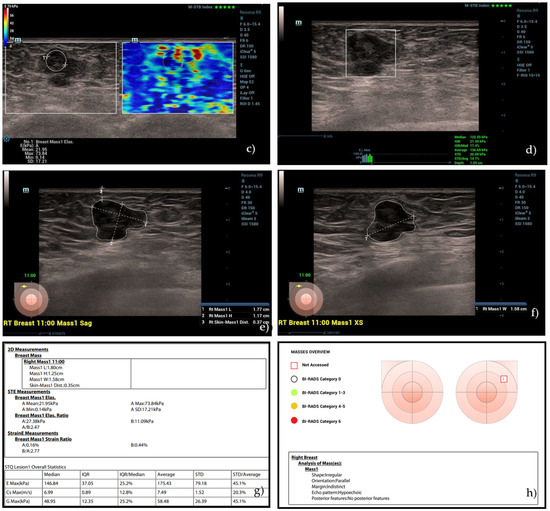

All breast nodules included in the study were subsequently evaluated by a second investigator by means of a B-mode ultrasound, color Doppler, and analysis performed by the semi-automatic “SmartBreast” software (Mindray, Resona R9, 3–14 MHz transducer). The investigator was blinded to mammographic and previous ultrasound results. The analyses by “SmartBreast”, in particular, involved the following parameters provided by the BI-RADS lexicon for each lesion: dimensions (mm), shape (oval, rounded, irregular), orientation (parallel, not parallel), margins (circumscribed or not circumscribed: indistinct, angular, microlobulated, spiculated), echo-pattern (anechoic, isoechoic, hypoechoic, hyperechoic, heterogeneous, complex cystic, and solid mass), posterior features (no features, enhancement, shadowing, combined pattern), microcalcifications, and vascularization at color Doppler (absent, peripheral, internal). All these ultrasound features were automatically detected and analyzed by the software, which, at the end, provided a summary table with the determination of a BI-RADS category and the consequent probability of benignity or suspicion of malignancy (Figure 1).

Figure 1.

Mass overview with BI-RADS score provided by “SmartBreast”.